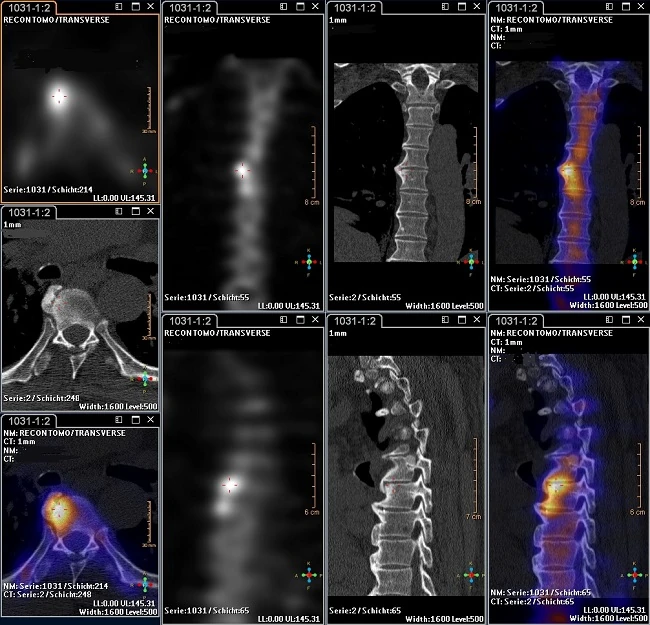

CT-Korrelation mit Bildfusion (SPECT-CT)

Die Kombination der SPECT-Technik mit der Computertomographie (CT) ermöglicht weitere diagnostische Möglichkeiten. Mit der SPECT-CT-Technik kann durch Fusionsbilder aus dem Funktionsbild der Szintigraphie und der strukturellen Informationen aus der CT eine genaue räumliche Zuordnung gewonnen werden.

aktivierte Spondylarthrosis L5/S1